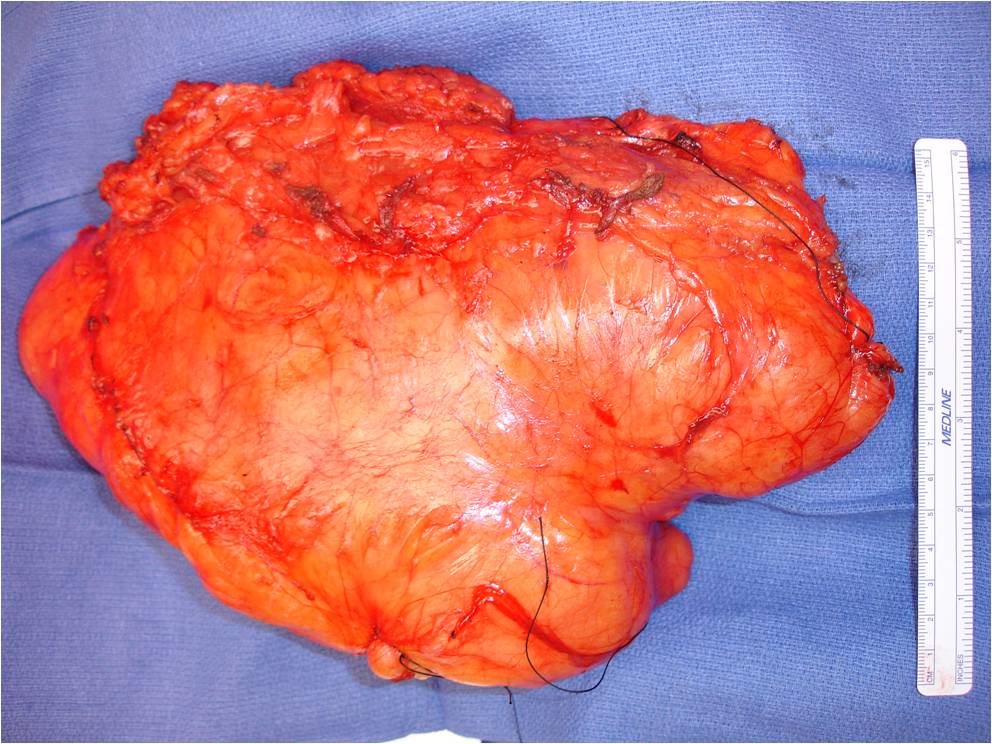

Gross

• Soft yellow fatty mass indistinguishable from normal fat

• Well circumscribed

• Lobular growth in some lipomas

• May have a significant fibrous component reflected as white tissue

• Muscle fibers may be present with intramuscular lipomas